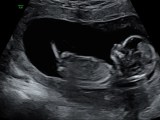

Big Update!

I am 17 weeks pregnant with a mysterious baby girl who decided to nestle in my belly one month before I turned 40. We found out on Christmas Day; I was just making sure I was good to drink at a family gathering when I saw the faint second line appear. “It won’t stick,” I … Continue reading